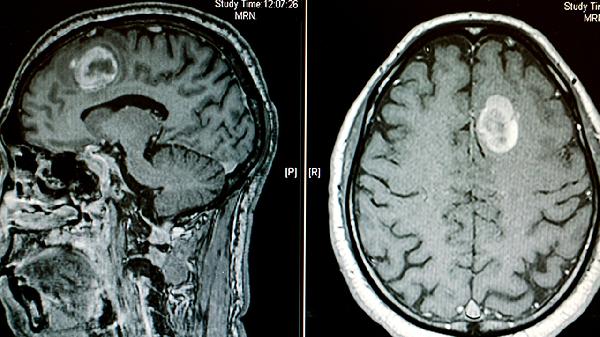

中枢或周围神经损伤会导致肌肉失去神经支配,引发废用性萎缩。脊髓损伤、中风、周围神经病变等疾病可能破坏神经信号传导,使肌肉无法正常收缩。早期表现为肌力下降,逐渐发展为肌肉体积缩小。需通过神经电生理检查明确诊断,治疗包括神经营养药物、康复训练等。